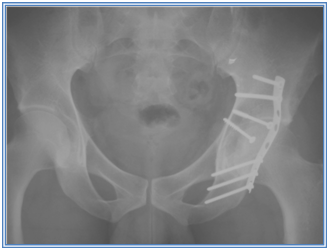

Due to it’s juxta-articular location, the bullet needed to be removed. We did not consider approaches through the joint, arthroscopic or open, as the bullet was buried sub-chondrally. A clinical decision was made that the best approach would be to perform an osteotomy of the posterior wall as this would minimize damage to the acetabular articular cartilage and the capsule would be left undisturbed. We could however find no reference in the literature to this. We proceeded with the osteotomy through a Kocher-Langenbeck approach to the acetabulum. The bullet was removed and the osteotomy reduced and fixed with two interfragmentary screws and a buttress plate (Figure 3). A standard post-operative regime for posterior wall fixation was followed.

Figure 3 The osteotomy was reduced and fixed with two interfragmentary screws and a buttress plate.

At 2 years follow up the osteotomy site had united with no complications and the patient had regained a pain-free full range of motion, could walk unaided and had no limp.